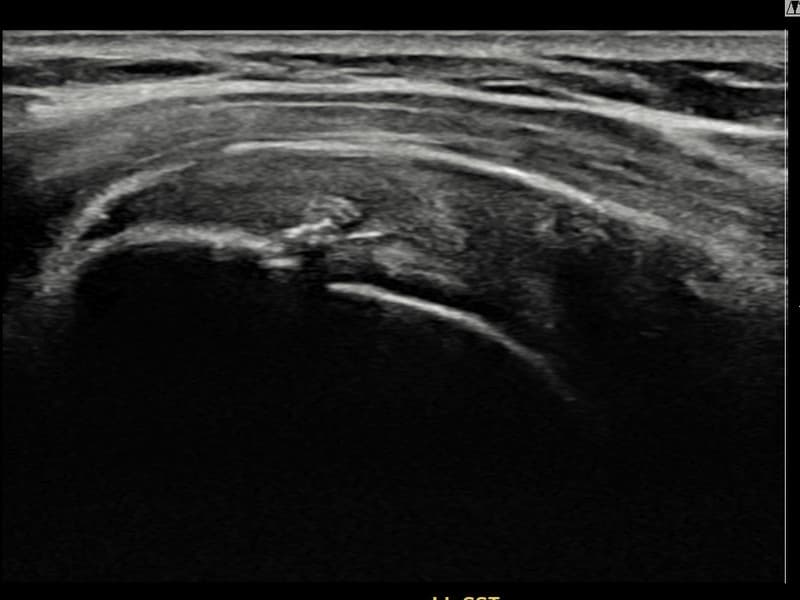

术后

术前超声确认左侧 冈上肌腱 关节面侧部分撕裂,左侧冈上肌腱回声不连续伴肌腱缺损(8mm × 3mm (肌腱厚度约30%缺损))。术后超声显示撕裂部位充满再生组织,肌腱连续性恢复,回声模式正常化。